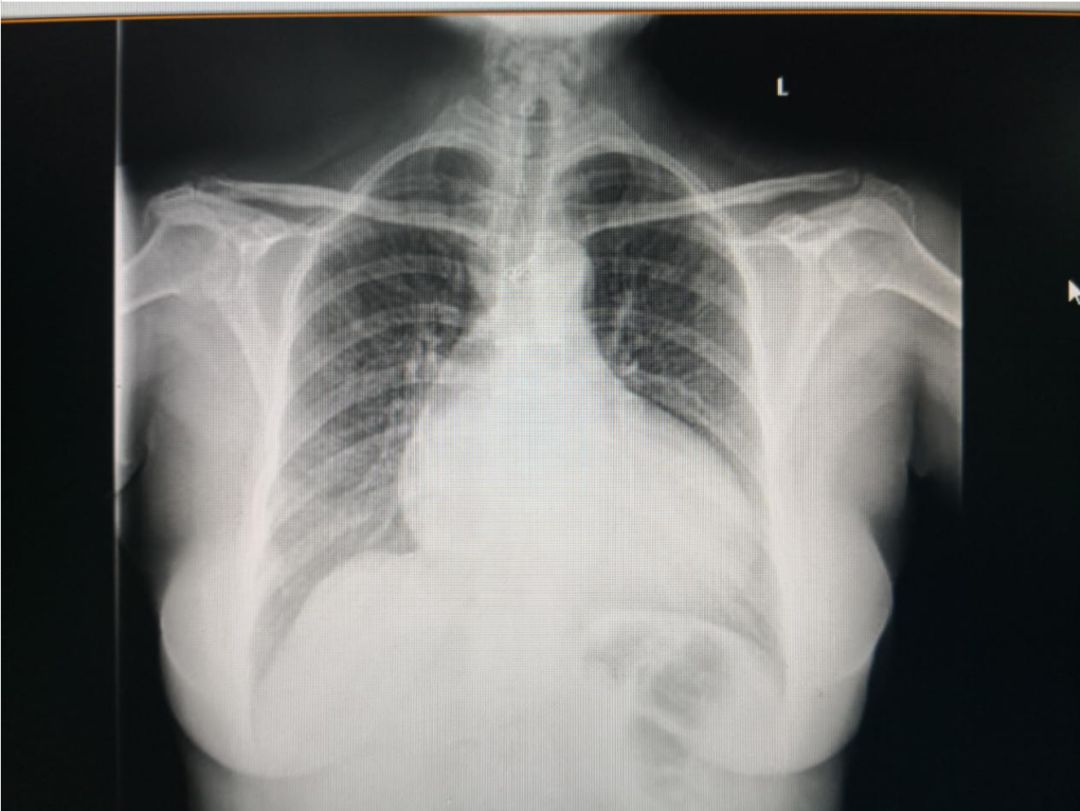

胸片: 双肺纹理增多,心影增大,心胸比约为0.67,主动脉钙化。

图3:患者入院胸片检查结果